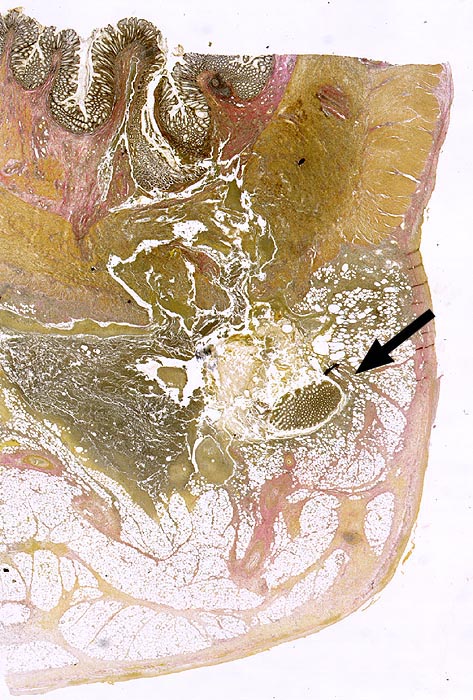

PathoPic ID 626 - Divertikulitis

Divertikulitis

Entzündung infektiös

Kolon Sigma

Darm, Anus

Partiell entzündlich zerstörtes Divertikel mit abszedierender Entzündung und

►

erhaltener Schleimhautinsel.

Histologie

Scan

70